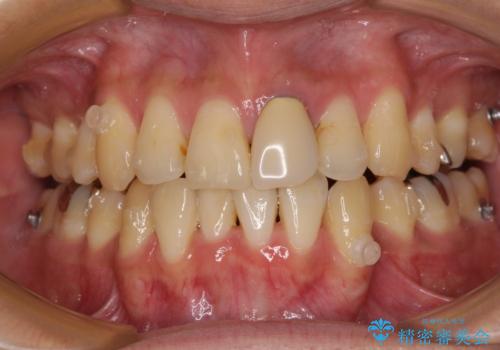

- 下顎の八重歯を気にして来院された患者様です。

左下以外、3本の第一小臼歯が既に抜去されており、左下は八重歯になっている状態でした。

左下の八重歯は手前に傾斜していたため、インビザラインによる抜歯矯正が可能と判断し、後方にある第一小臼歯を抜歯してインビザラインにて矯正治療を行うこととしました。

ワイヤー矯正と比較すると、八重歯が後方に傾斜した仕上がりとなりましたが、患者様ご希望のインビザラインにて十分な歯列を達成することができました。